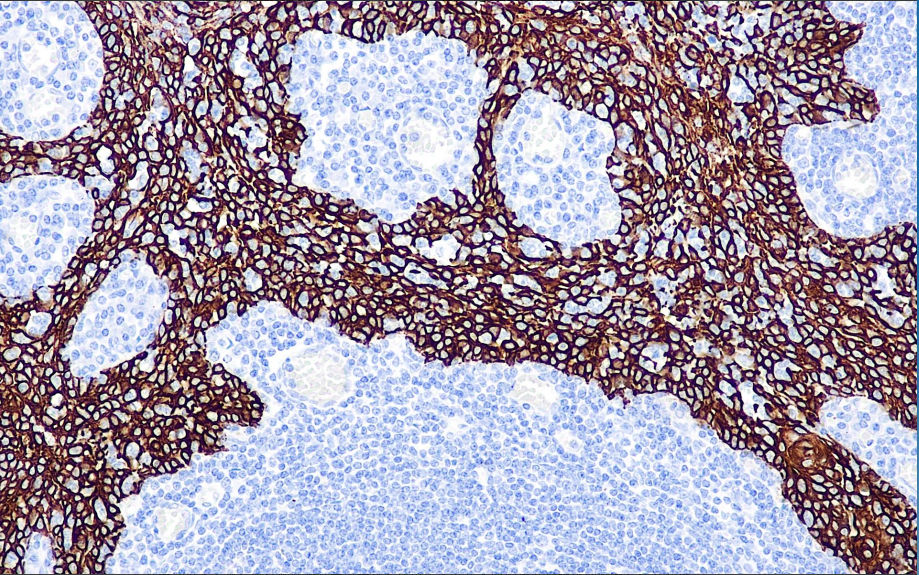

In normal tissues, it can label basal cells of squamous and ductal epithelium as well as part of squamous epithelial germinal layer cells, myoepithelial cells and mesothelial cells, and is not expressed by adenoepithelial cells. Therefore, it can be used for the differential diagnosis of squamous carcinoma and adenocarcinoma, and mesothelioma and adenocarcinoma. It can also be used in the differential diagnosis of benign and malignant hyperplasia of ductal epithelium.

CK5 or 6 antibody reagents can specifically bind to CK5 or 6 molecular antigens. Immunohistochemistry kits containing CK5 or 6 antibody reagents are suitable for the auxiliary diagnosis of squamous cell carcinoma, adenocarcinoma, and mesothelioma, among others.